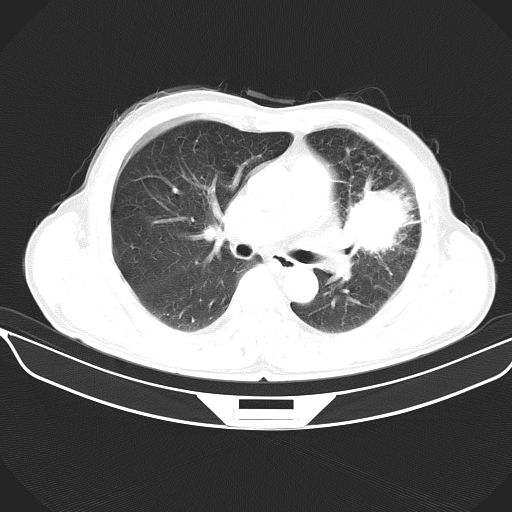

以下是引用心路寻觅在2010-3-1 10:23:00的发言:[br]1、考虑左肺上叶周围型肺癌[br]2、右上肺陈旧性病灶。[br][br][本贴已被 心路寻觅 于 2010-3-1 10:40:18 修改过]

以下是引用shuiyuan在2010-3-1 10:45:00的发言:[br]考虑左肺上叶中心型肺癌伴阻塞型炎症,邻近胸膜受侵。